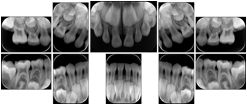

Table OO.1.1-1 shows structured display standard templates, where Viewset ID is based on the Japanese Society for Oral and Maxillofacial Radiology (JSOMR) classification provided by JIRA (Japan Medical Imaging and Radiological Systems Industries Association, www.jira-net.or.jp). Expected or typical teeth to be imaged location, region and designation codes are based on ISO 3950-2010, Dentistry - Designation system for teeth and areas of the oral cavity. For all the hanging protocols listed in OO.1.1-1, the value to use for Hanging Protocol Creator (0072,0008) is "JSOMR" and the value to use for Hanging Protocol Name (0072,0002) does not include "JSOMR" (e.g., "DL-S001A", not "JSOMR DL-S001A").